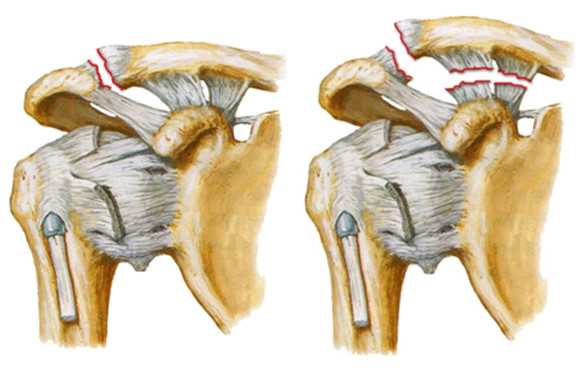

При подострой степени повреждения АКС нами выполняется модифицированная операция WEAVER-DUNN.

Дополнительно к установленным пуговицам, которые прижимают ключицу к клювовидному отростку, предварительно прошитая часть корако-акромиальной связки разворачивается и фиксируется к ключице. Таким образом производится несвободная пластика ключично-клювовидных связок при помощи акромиально-ключичной связки.

Модифицированная операция WEAVER-DUNN непроста для исполнения. Для проведения ее при достаточной визуализации, требуется анестезиологическое обеспечение высокого уровня, которым наша клиника оснащена.